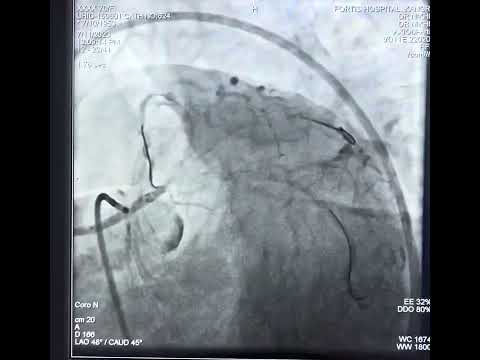

PCI of Calcified LM Trifurcation Lesion - Rotational Atherectomy & 2-Stent - CCC Live May 2017